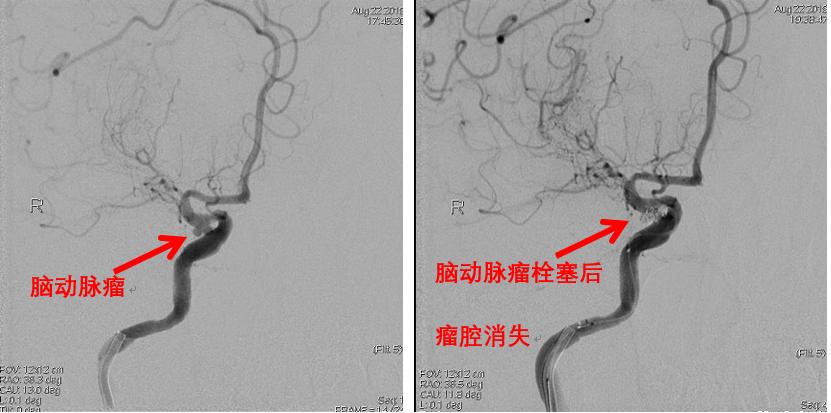

神经血管篇——脑动脉瘤

深藏颅内的脑动脉纤细而又敏感,各种因素导致它们局部薄弱后形成脑动脉瘤,一旦薄弱的管腔破裂,患者凶多吉少。神经外科医生要打开颅骨,分离脑组织,充分暴露后,夹闭出血点。而血管介入医生则另辟蹊径,利用导管将栓塞材料从血管内填充至破裂出血处,可谓直捣黄龙。

脑动脉瘤介入治疗